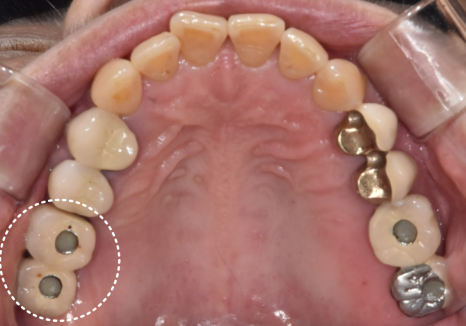

오래전 타치과에서 오른쪽 위

어금니 두 곳(#16, #17)에

임플란트를 심으셨던

환자분이 찾아오셨습니다.

230216

"맨 끝 어금니 앞쪽(#16)이 욱신거리고,

누르면 뭐가 나와요."

불편함을 호소하시는 환자분의 입안을 보니,

상황은 생각보다 좋지 않았는데요..

잇몸은 붉게 부어올라 있었고,

살짝만 눌러도 노란 고름이 배어 나오는 상태...